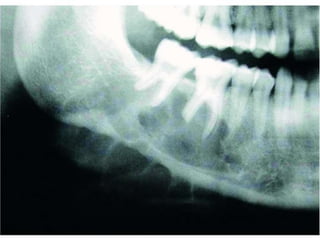

Ameloblastoma

 Radiographic findings

 Classic – multilocular radiolucency of posterior

mandible

 Well-circumscribed, soap-bubble

 Unilocular – often confused with odontogenic cysts

 Root resorption – associated with malignancy